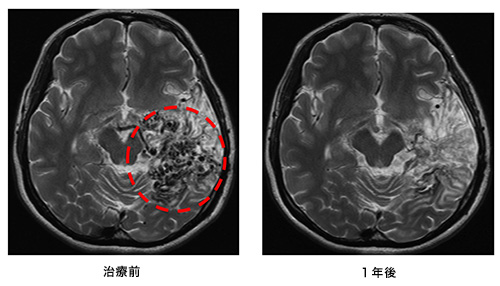

脳出血による半身麻痺と意識障害で発症した患者さまの治療前後の血管撮影を下に示します。(赤線内が脳動静脈奇形の部分)